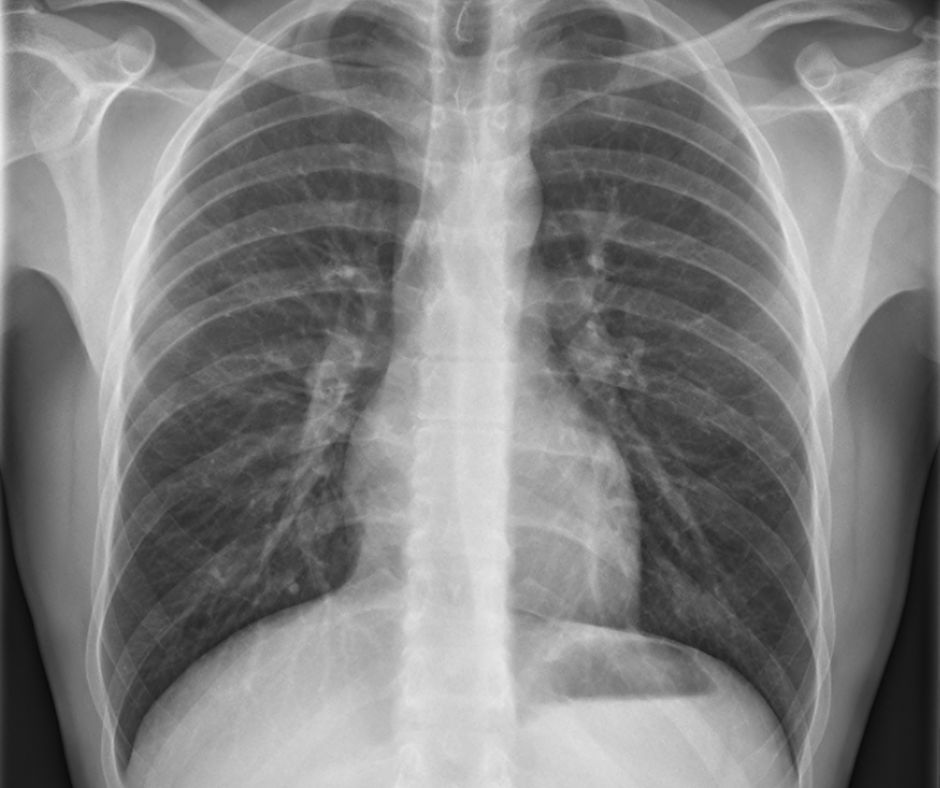

Röntgenové snímky hrudníka: Môžu byť použité na vylúčenie iných ochorení, ktoré môžu spôsobiť podobné symptómy, ako je napríklad pneumónia.